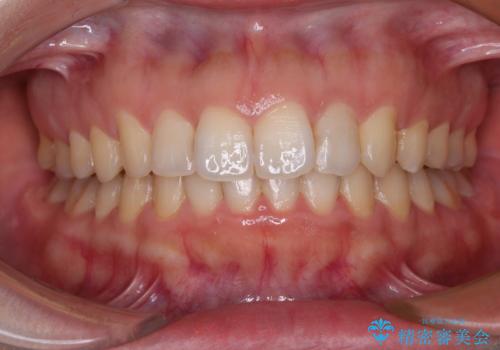

【モニター】捻れた前歯をスッキリと インビザライン矯正治療

- 前歯の捻れを気にして来院された患者様です。

上顎前歯が捻れて前方に飛び出しており、下顎前歯もそれに沿うようにデコボコとなっていました。

IPR(歯と歯の間を削る処置)によりスペースを獲得して下顎前歯のデコボコを改善し、上顎前歯は下顎前歯と接する位置にまで引っ込めるように設定し、インビザラインにて矯正治療を行うこととしました。

しっかりと装着時間を守ってくださったので、予定通り1年強で治療を終えることができました。